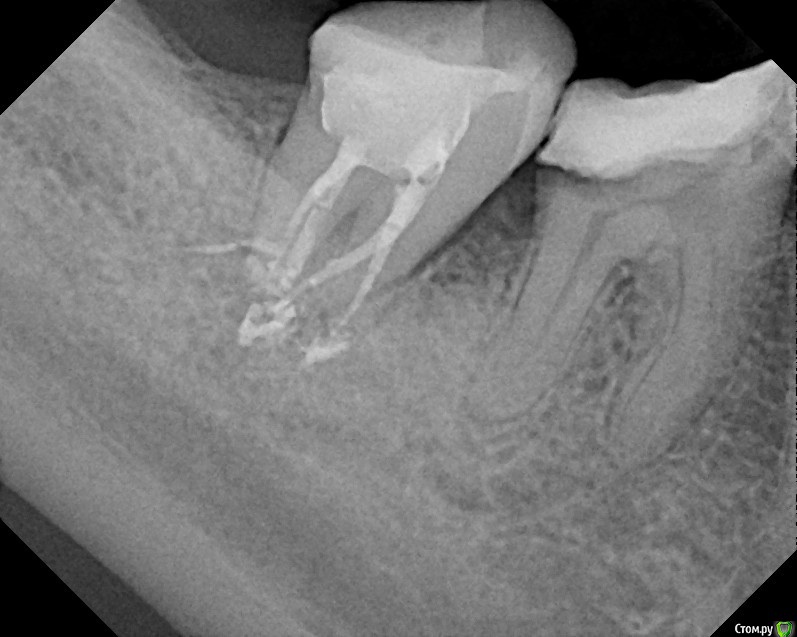

St616 Опубликовано 1 декабря, 2014 Поделиться Опубликовано 1 декабря, 2014 (изменено) Добрый день ! Прошу вас посмотрите пломбировку каналов метапексом После пломбировки 2 дня сильная боль при нажатии и вообще.Сегодня пятый день, зуб поднывает и еще качается. Дело в том что у меня грудной ребенок, я его кормлю и поэтому не хотелось может более сильных, но не безопасных средств. Нервы удаляли с анастезией без лекарств. Тк был предложен только мышьяк. А у меня ребенок га гв. Пломбировка каналов и окончатильная очистка уже через 7 дней в другой клинике, хотели гуттаперчей. Но тк зуб качался сделали метапексом, врач вроде хоть и молодой но оч грамотный. Меня волнует небольшое темное пятно в одном канале под пломбой, это что воздух там? Не из ха этого ди боль сохраняется, сейчас уже небольшая. Воач по снимку сказал, что всё хорошо, а боль из за того что метапекс вышел за пределы. Фото до и после Изменено 1 декабря, 2014 пользователем St616 Ссылка на комментарий